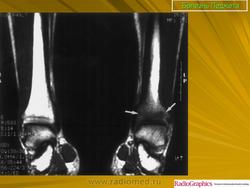

Педжета болезнь (J. Paget англ. хирург, 1814-1899; синоним: деформирующий остоз, деформирующий остит, деформирующая остеодистрофия) - заболевание скелета, при котором наблюдается поражение одной или нескольких костей в результате патологической перестройки костной ткани.

Принято различать три фазы развития П. б.: очаговая интенсивная резорбция кости (остеолитическая, или деструктивная, фаза), смешанная фаза, когда наряду с рассасыванием кости идут процессы новообразования ее, и остеобластическая, или склеротическая, фаза с образованием типичных мозаичных структур.